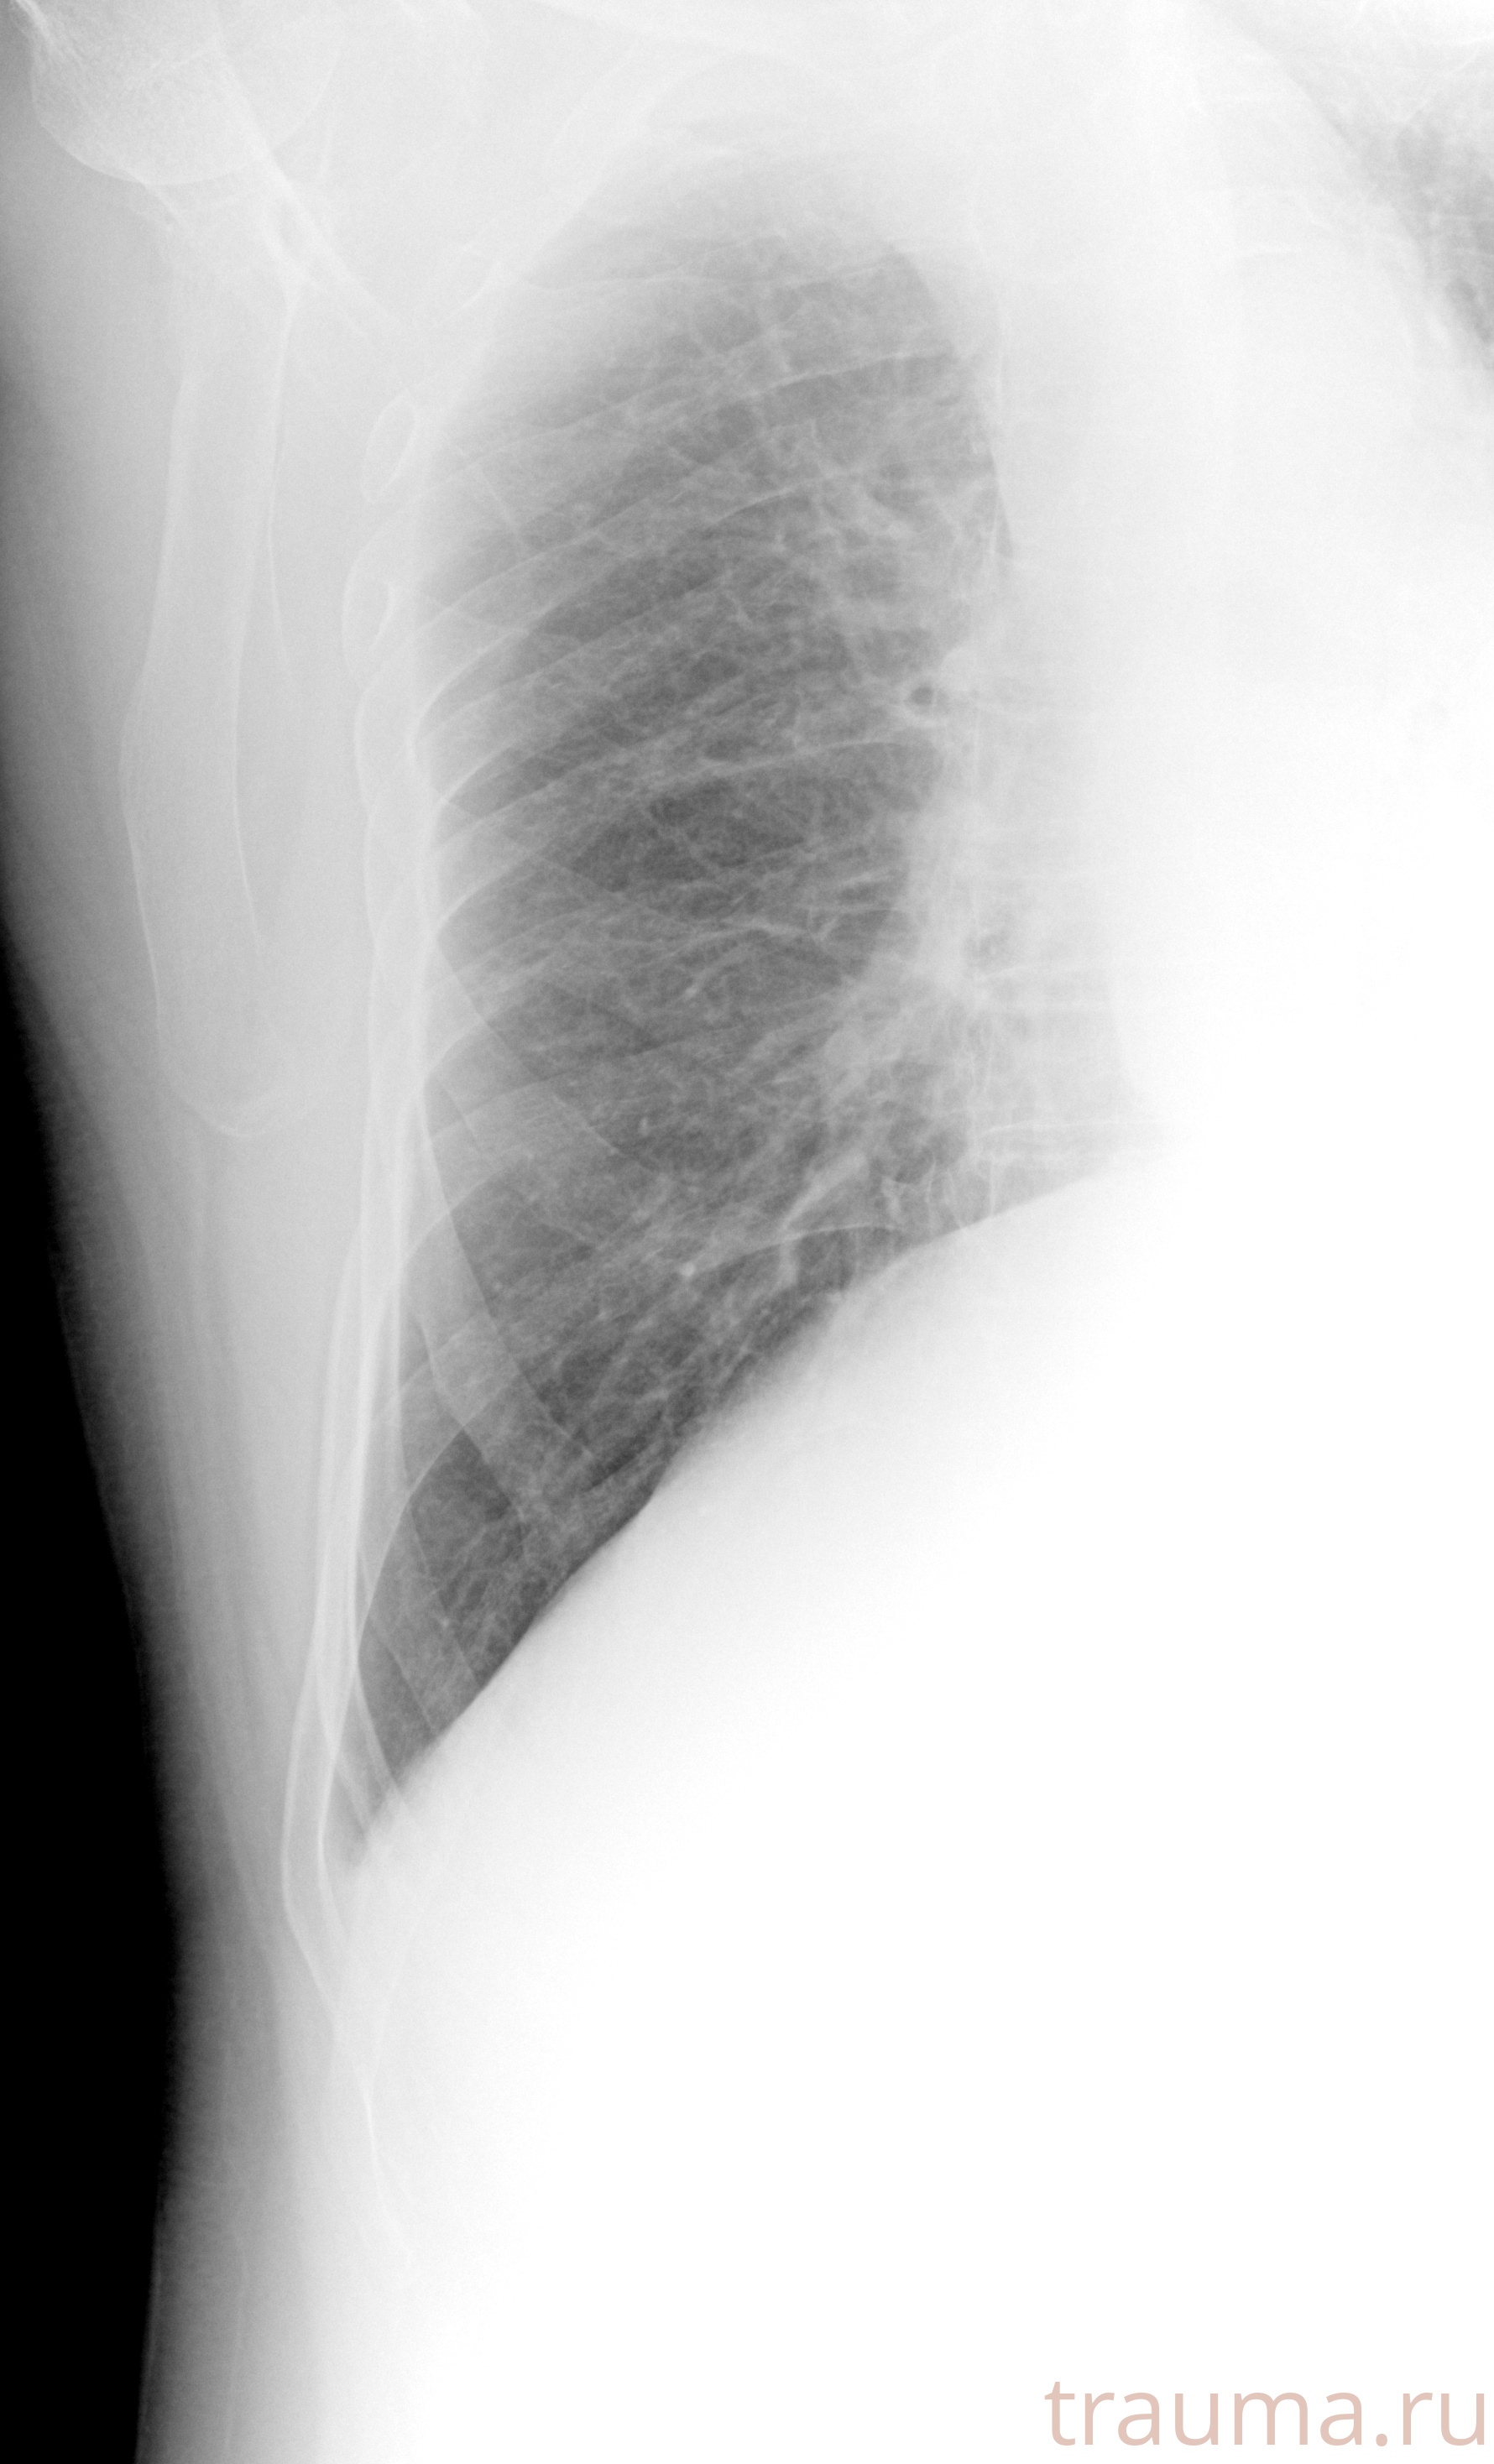

Рентгенограммы

Рентген на дому: по вашему адресу приезжает врач-рентгенолог, травматолог-ортопед с мобильным рентгеновским аппаратом, проводит диагностику травмы или заболевания, делает необходимые рентгенограммы, дает рекомендации по дальнейшему лечению. Получить качественные снимки в домашних условиях возможно благодаря уникальной методике, разработанной МосРентген Центром для института  Склифосовского

Яркость: 1   Контраст: 1   Инвертировать: 0 Увеличение: 1

Перетаскивайте мышь вверх/вниз для контраста, влево/право для яркости. Прокрутка колесом изменяет масштаб. Нажмите Сбросить для возврата к исходному изображению. При увеличении держите мышь в той области, которую хотите рассмотреть.

при переломе шейки бедра и пневмонии от компании МосРентген Центр - партнера Института имени Склифосовского